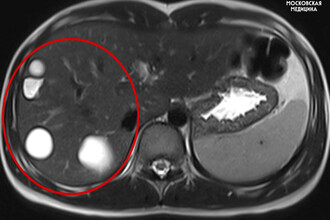

У московской школьницы случайно нашли в печени кисты с паразитами